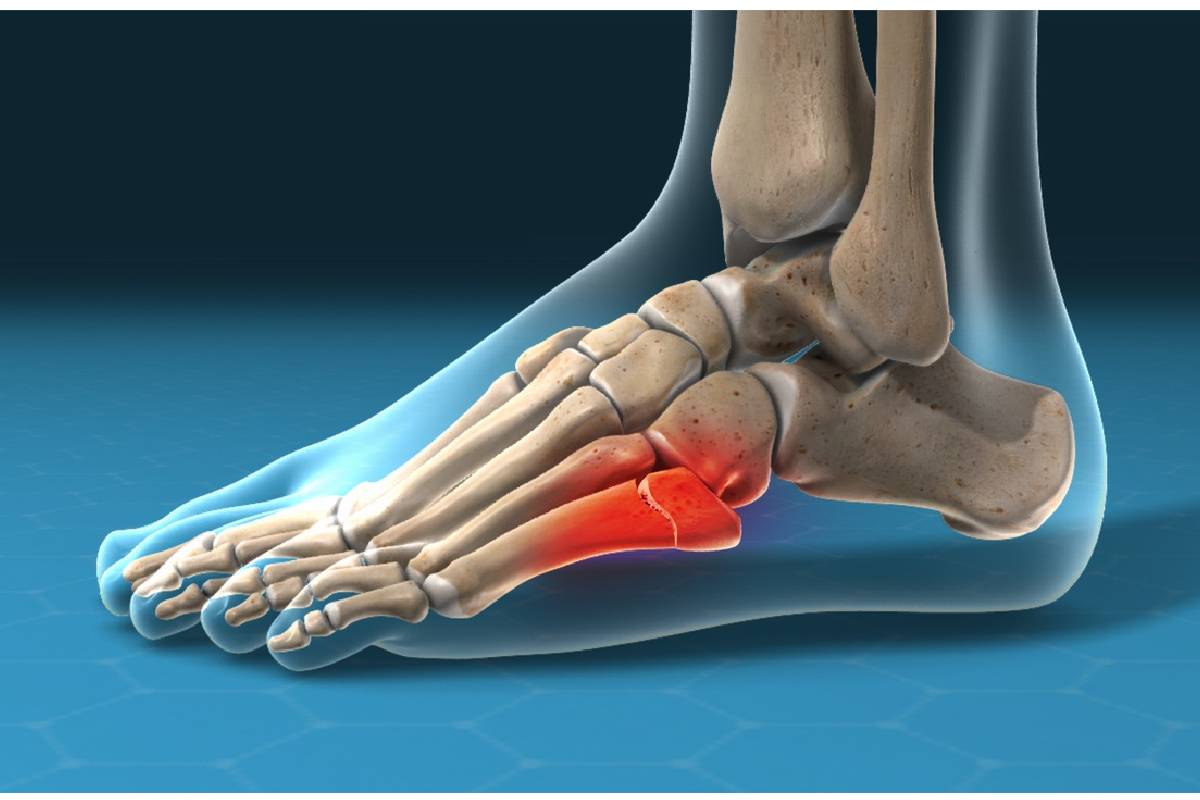

شکستگی جونز (Jones Fracture) یک شکستگی خاص در پایهی استخوان پنجم متاتارس پا است. این استخوان در بخش خارجی کف پا قرار دارد و شکستگی دقیقاً در نقطهای بین پایه و تنه اصلی استخوان اتفاق میافتد.

ویژگی اصلی که این شکستگی را از سایر شکستگیهای این استخوان متمایز میکند، محل آن است. این ناحیه به دلیل داشتن خونرسانی ضعیف، فرآیند بهبودی کندتری دارد. به همین دلیل، درمان آن ممکن است چالشبرانگیزتر باشد و گاهی خطر جوش نخوردن استخوان یا نیاز به درمانهای جدیتر وجود دارد.

این شکستگی در ناحیهای با خونرسانی ضعیف رخ میدهد و به همین دلیل درمان آن دشوارتر است و احتمال بروز عوارض در آن بیشتر است.